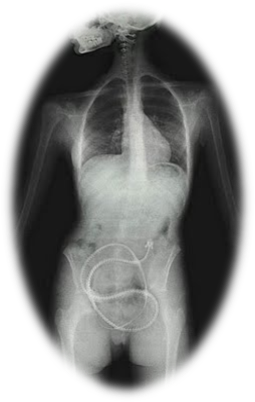

Teníase

2. CAUSAS

1. Ingestão

1. Carne

1. Crua

1. Mal

1. Passada

2. ORIGEM

1. Parasita

1. Ténia

1. Habitat

1. Intestino

1. Humano